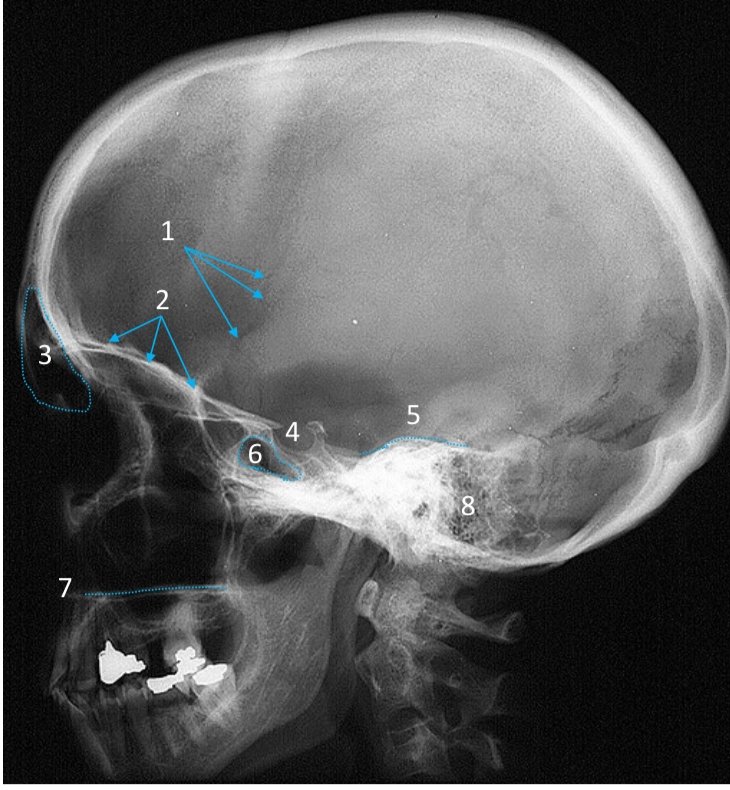

Mandible

ID bone

Maxilla

ID bone

Frontal sinus

ID structure

Pituitary fossa

ID structure

Occipital

ID bone

Lambdoid suture

ID structure

Frontal sinus

ID structure

Orbital margin

Orbit

Maxillary sinus

ID structure

Mandibular condyle

ID structure

Inferior nasal concha

ID structure

Hard palate

ID strucutre

Gonial angle

ID strucutre

Petrous ridge

ID structure

Groove of middle meningeal a.

ID structure

Roof of orbit

ID structure

Frontal sinus

ID structure

Pituitary fossa

ID structure

Petrous ridge

ID structure

Sphenoid sinus

ID structure

Hard palate

ID structure

Mastoid air cells

ID structure

Zygomatic arch

ID structure

Mandibular condyle

ID structure

External auditory meatus

ID structure

Mastoid air cells

ID structure

Foramen magnum

ID structure

Foramen ovale

ID structure

Foramen spinosum

ID structure